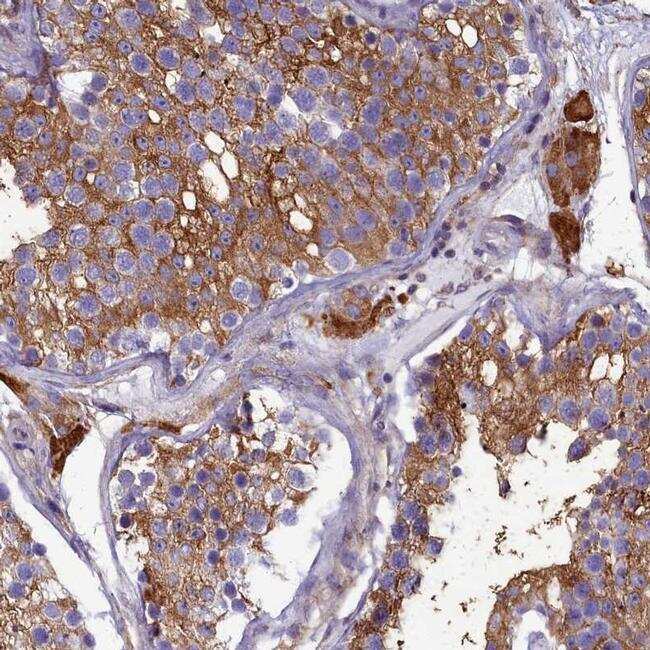

- Immunohistochemical analysis of SLC26A10 in human testis using SLC26A10 Polyclonal Antibody (Product # PA5-60801) shows strong cytoplasmic positivity in cells in seminiferous ducts and Leydig cells.